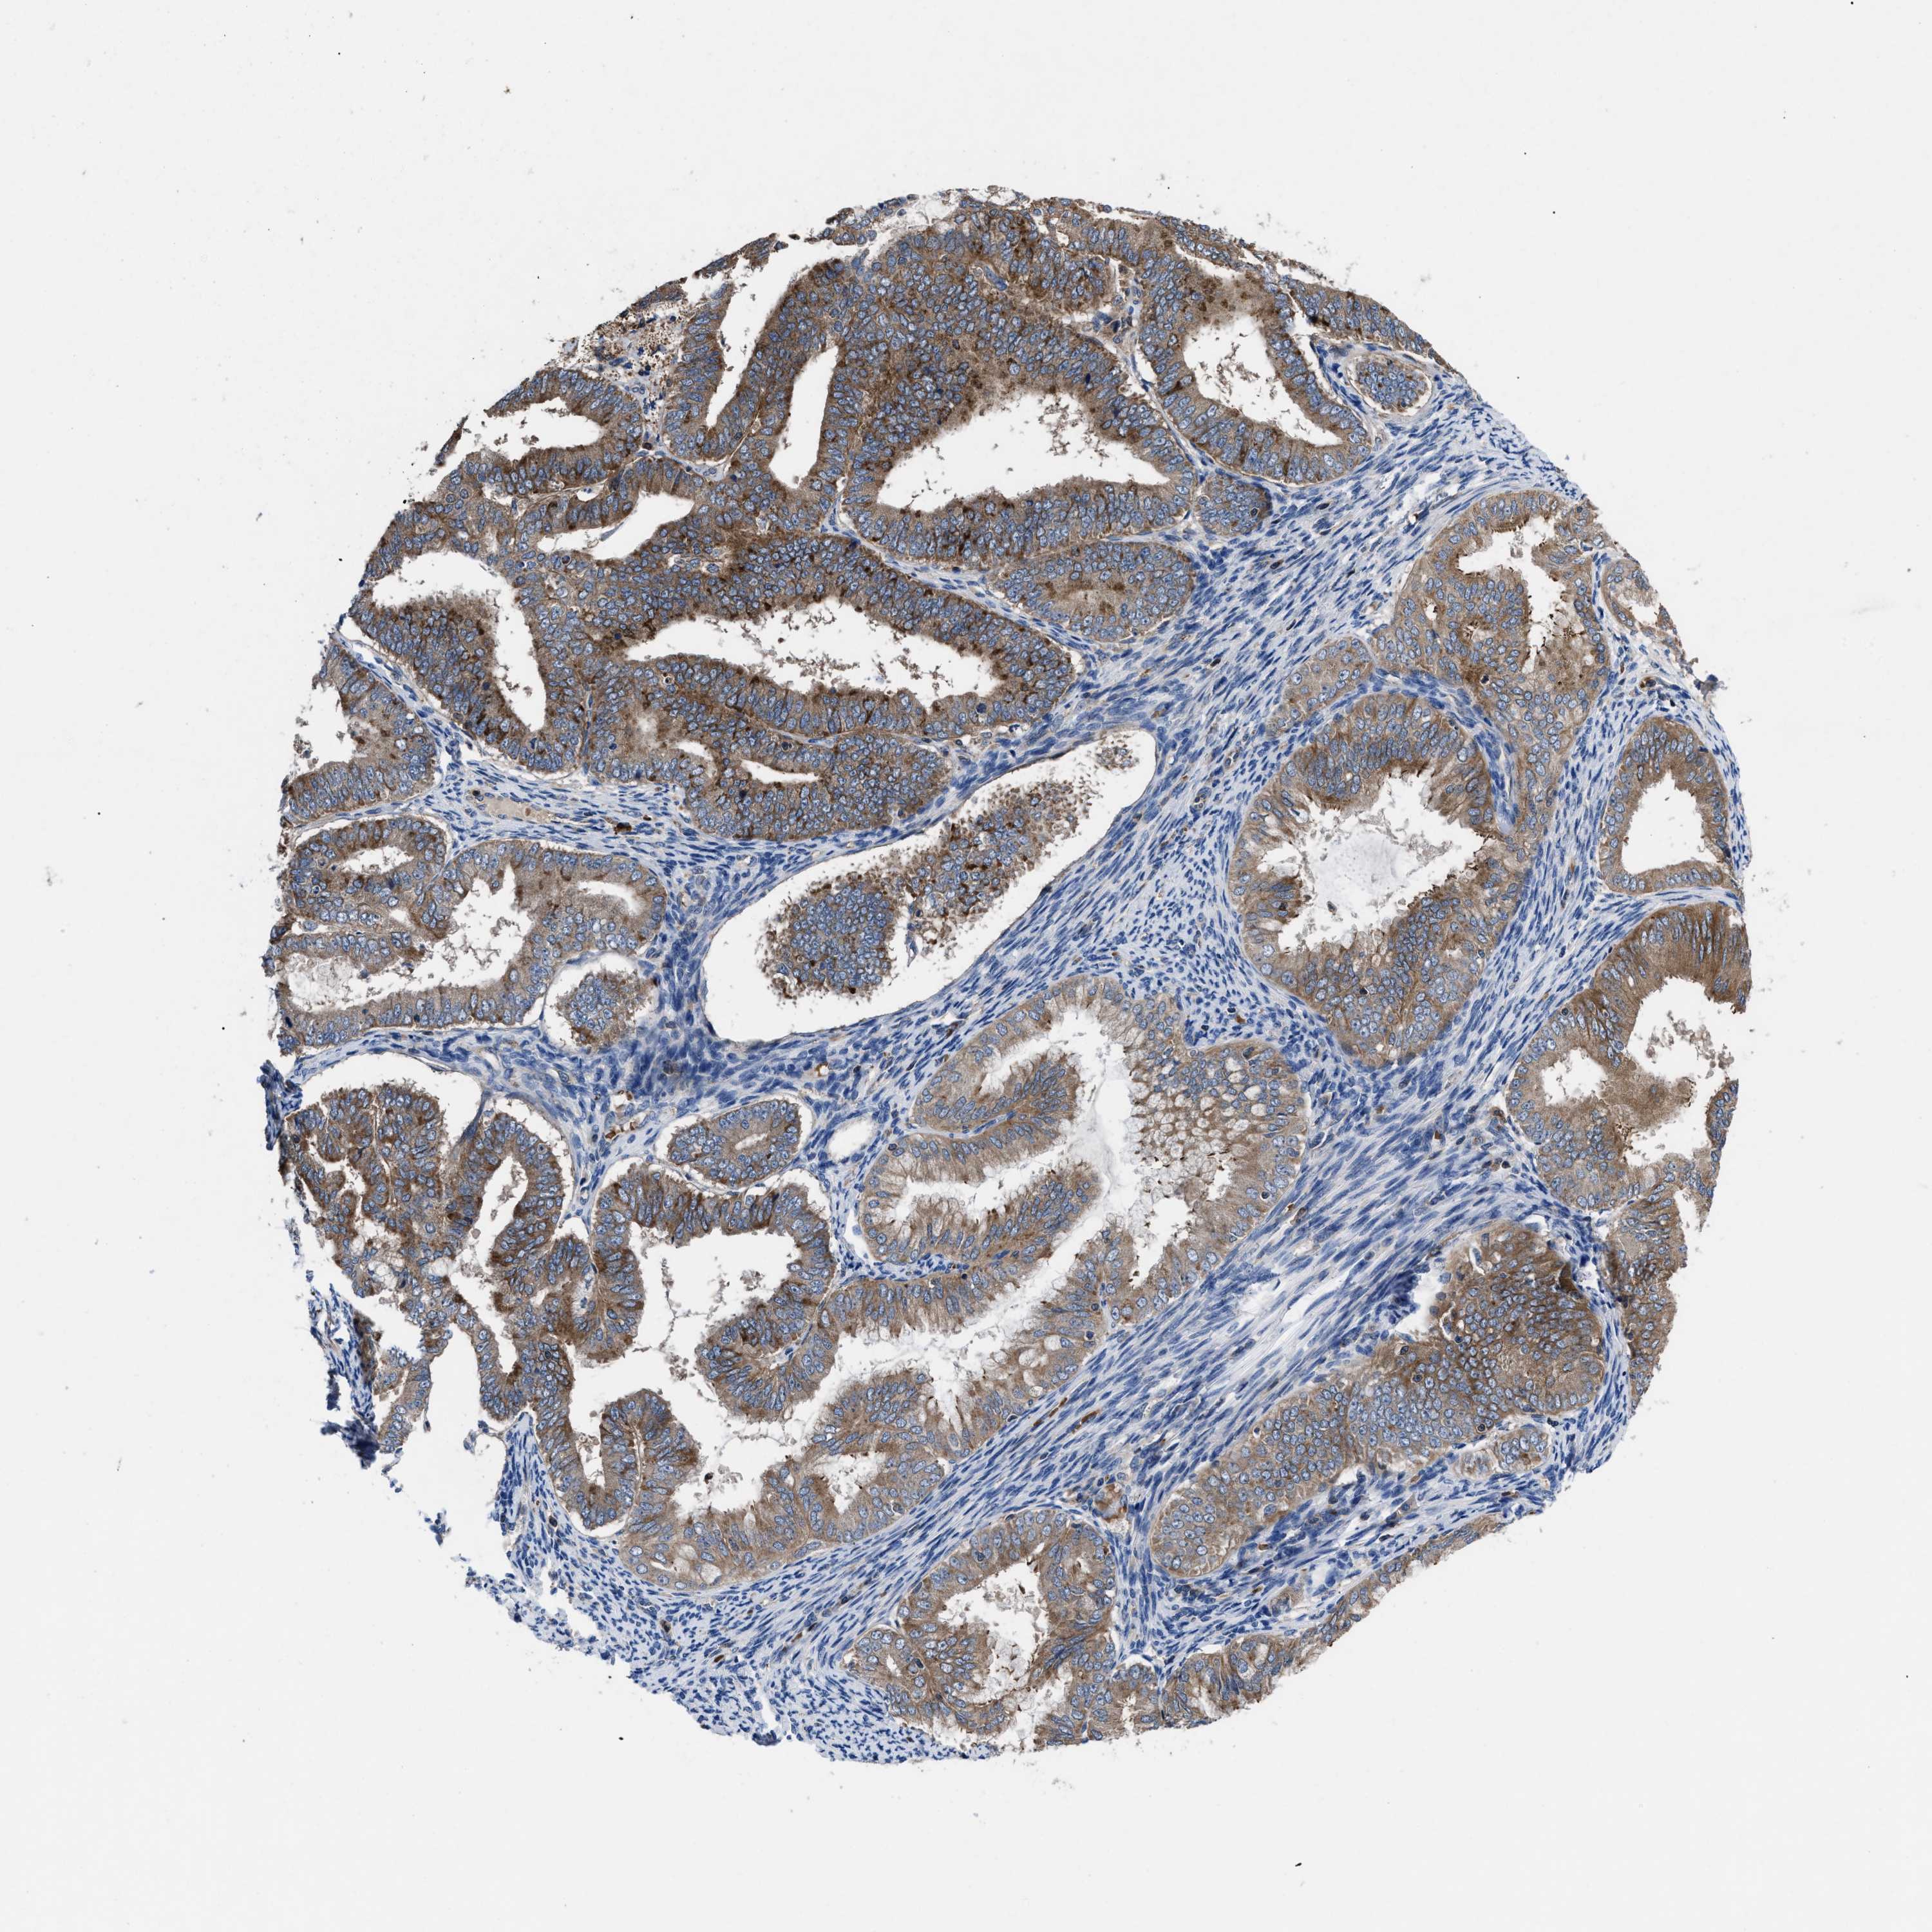

ENDOMETRIAL CANCER - Protein expressioni

A mouse-over function shows sample information and annotation data. Click on an image to view it in a full screen mode. Samples can be filtered based on level of antibody staining by selecting one or several of the following categories: high, medium, low and not detected. The assay and annotation is described here.

Note that samples used for immunohistochemistry by the Human Protein Atlas do not correspond to samples in the TCGA dataset.

Antibody stainingi

Antibody staining in the annotated cell types in the current human tissue is reported as not detected, low, medium, or high, based on conventional immunohistochemistry profiling in selected tissues. This score is based on the combination of the staining intensity and fraction of stained cells.

Each image is clickable and will lead to virtual microscopy that enables deeper exploration of all samples and also displays staining intensity scores, fraction scores and subcellular localization as well as patient and tissue information for each sample.

Antibody HPA018162

Staining

High

Medium

Low

Not detected

Intensity

Strong

Moderate

Weak

Negative

Quantity

>75%

75%-25%

<25%

None

Location

Nuclear

Cytoplasmic/membranous

Cytoplasmic/membranous,nuclear

Adenocarcinoma, NOS